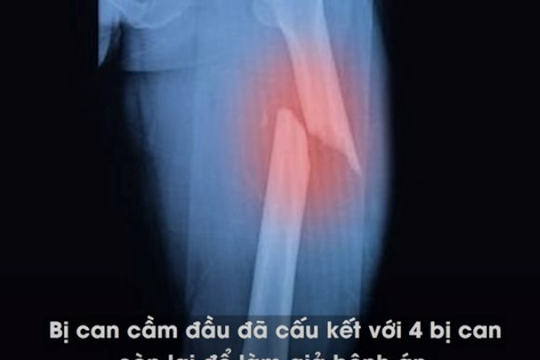

Tiêm thuốc mê, sau đó dùng búa đinh tác động vào xương chậu, xương đùi để trục lợi bảo hiểm

Tạ Minh Châu tiến hành tiêm thuốc mê vào tĩnh mạch của các đối tượng, sau đó dùng búa đinh tác động trực tiếp vào các vùng xương chậu, xương đùi để tạo tổn thương nghiêm trọng để yêu cầu các công ty bảo hiểm chi trả tiền bồi thường tai nạn.